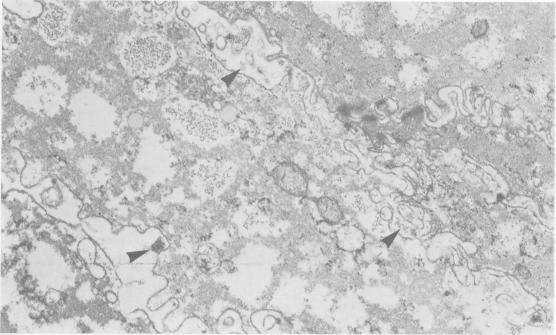

Effects of bile acids and hydrogen ion on the fine structure of oesophageal epithelium.

Oesophageal mucosal biopsies were incubated in 20, 0, and 0.2mM solutions of cholic, chenodeoxycholic, ursodeoxycholic, and deoxycholic bile acids. Both conjugated and unconjugated bile acids were studied at pH 1 and 7 singly and in combination. Observations were also made using 0.1 N hydrochloric acid and human gastric juice at pH 1-3 and 7-8. After incubation for up to 15 minutes the mucosa was examined under transmission electron microscopy. We concluded that high and moderate concentration of all the common bile acids damaged the oesophagus irrespective of the pH, that low concentrations of bile acids were damaging only at high acid levels, and that damage to the epithelium did not occur when the pH of the gastric juice had been raised.